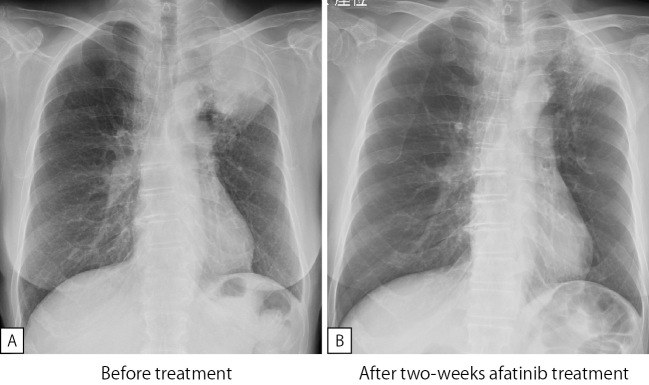

The Afatinib Response to EGFR E709G-mutated Lung Cancer.